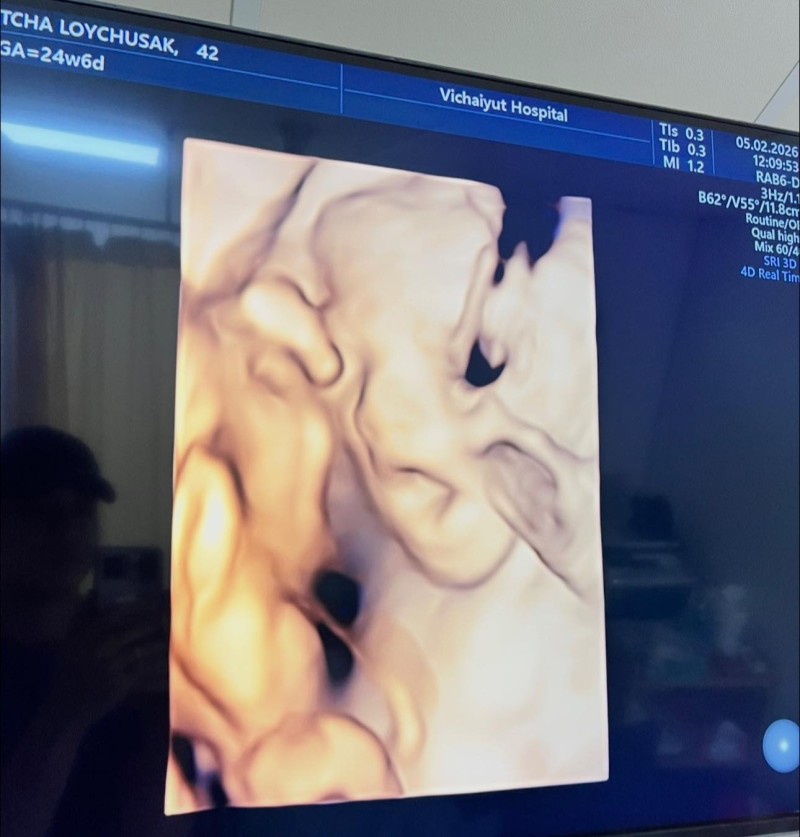

เรียกได้ว่าทำเอาแฟนคลับ ยิ้มตามกันไม่ไหว เมื่อ เจมส์ เรืองศักดิ์ ลอยชูศักดิ์ ออกมาอัปเดตความอบอุ่นของครอบครัว ด้วยการเผยภาพอัลตราซาวด์ลูกสาวคนที่ 2 น้องมีเมตตา จากภรรยาคนสวย ครูก้อย นัชชา ซึ่งขณะนี้อายุครรภ์ครบ 6 เดือนแล้ว ภาพดังกล่าวเผยให้เห็นใบหน้าของน้องมีเมตตาอย่างชัดเจน ยิ้มหวาน จมูกโด่ง น่ารักน่าชังตั้งแต่อยู่ในท้อง

โดยคุณพ่อเจมส์เขียนแคปชันด้วยความเอ็นดู พร้อมยืนยันจากแพทย์ผู้ดูแลว่าลูกน้อยแข็งแรงสมบูรณ์ พัฒนาการเป็นไปตามเกณฑ์ทุกด้าน งานนี้แฟนคลับ แห่กดไลก์และคอมเมนต์ร่วมแสดงความยินดี พร้อมเอ็นดูความน่ารักของว่าที่สมาชิกใหม่ของครอบครัวกันอย่างล้นหลาม